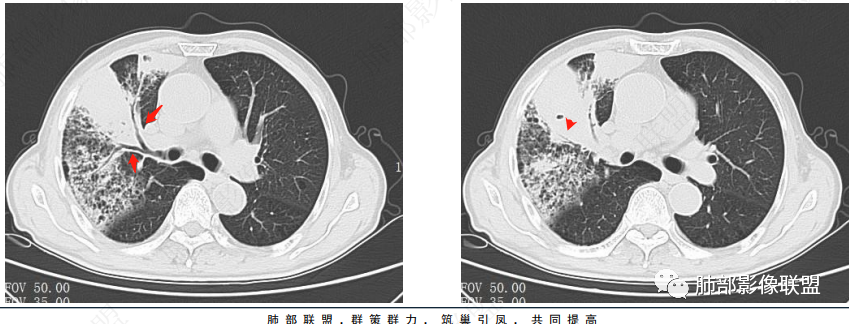

两个病灶独立,又有关联性,内侧病灶近端的支气管包绕在外侧病灶之中,但是走形自然

内部大片坏死区,其中还有不规则空洞

坏死腔内壁清,有强化环

肺动脉在实变区走形自然,坏死腔周围受压推移,走形自然,坏死区内破坏

这类坏死区内空洞,提示坏死液比较粘稠

不是液化坏死,液化坏死,这么大,有气体进来按理会形成液气平面

凝固性坏死